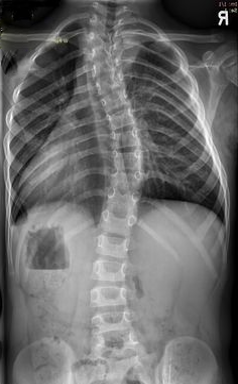

שיעור העקמת נמדד על פני צילום רנטגן הנעשה בעמידה וכולל את כל עמוד השדרה ורכס האגן. העקמת נמדדת במישור הצידי מהחוליה העליונה ועד התחתונה בעקמת. שיעור העקמת והפוטנציאל להחמרתה הם המשתנים עליהם מבוססת ההחלטה לטיפול במחוך. עקמת מעל 20 מעלות היא עקמת שמצדיקה התאמת מחוך - כל עוד קיים פוטנציאל גדילה אצל המטופל/ת. הסיכון להחמרה בעקמת תלוי לכן בגיל הנער/ה, מידת התפתחות/ה, וגיל העצמות. ככל שהגיל צעיר יותר כך קיים סיכון רב יותר להחמרה של העקמת במהלך הגדילה. כך למשל נער/ה בגיל 16 המגיעים עם עקמת בת 30 מעלות לא יתאימו לטיפול במחוך משום שסיימו קרוב לוודאי את גדילתם ואין חשש להחמרה בעקמת. בגלל הקושי בהחלטה על טיפול במחוך יש הממליצים לעקוב מספר חודשים אחר מידת השינוי בעקמת ואם אכן קיימת החמרה בשיעורה – ימליצו על טיפול במחוך.

צילום עמו"ש של עקמת גבית

נקודה נוספת נוגעת לשיטת המדידה והמעקב אחר העקמת. אין תחליף להדמיית עמוד השדרה על ידי צילום רנטגן. מדידת העקמת נעשית על גבי צילום רנטגן של עמוד השדרה ולא יכולה להיעשות על גבי MRI, אולטראסאונד או שיטות הדמיה אחרות שנוסו במהלך ההיסטוריה. החשש מקרינת רנטגן מוצדק לאור ריבוי הצילומים שאותם מטופלים עוברים במהלך המעקב. יש לציין שברוב המרכזים בהם מטפלים בעקמת, קיימים מכשירי רנטגן מופחתי קרינה שנועדו לצילומי העקמת. יש הצדקה לבקש ולבצע את צילומי המעקב עצמם תוך שימוש במכונות רנטגן ייעודיות לצילומי עמוד השדרה.